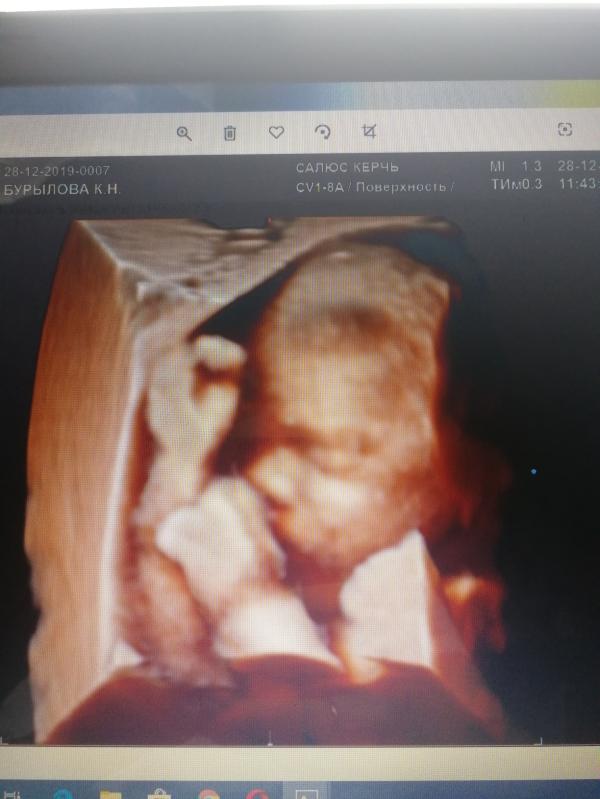

Все нормально вроде, только риск преэклампсии после 37 недели высокий